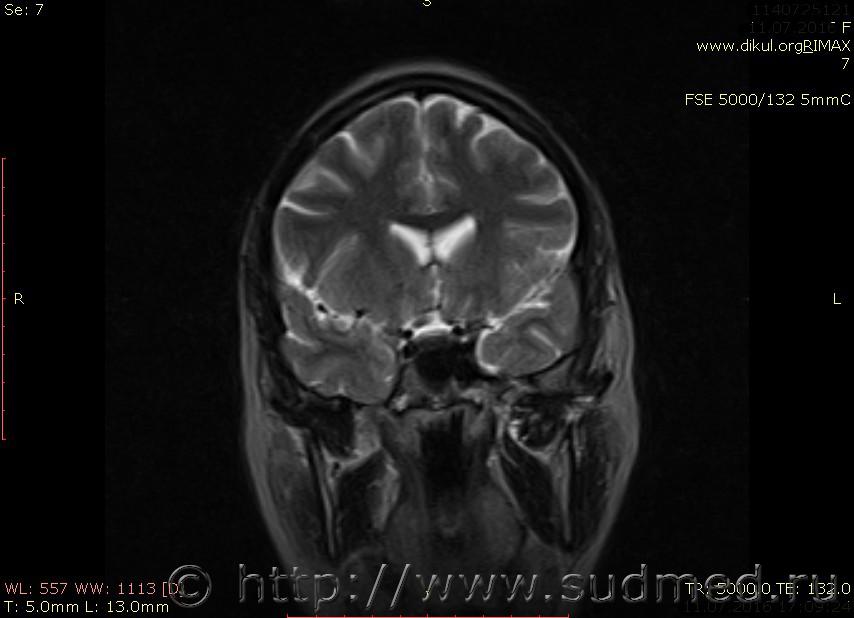

МРТ головного мозга показало: МР-данных за наличие очаговых изменений в веществе головного мозга на момент исследования не выявлено. МР-признаки нарушения соотношения в атланто-осевом суставе. Определяется ассиметрия положения зубовидного отростка С2 относительно боковых масс С1(справа 6,5; слева 4 мм.)

впрочем. есть и еще один момент - вывих С1! который не звучит в диагнозе невролога, хотя этот вывих - тяжкий вред здоровью.

Сама по себе эта информация даёт основания подозревать вывих первого шейного позвонка, но однозначно не свидетельствует о наличии вывиха. Нужно смотреть на снимках наличие реакции со стороны мягких тканей, в т.ч. связочного аппарата, нужно анализировать особенности неврологической патологии, её динамику и проч.

Запрошен электронный вариант снимков из учреждения, где делалось МРТ. Т.к. с самого снимка делать копии не получается,очень мелкие кадры. Завтра попробую вставить в сообщение. (Но СМЭ снимок не смотрел, смотрел только мед.карту, в которой находилось описание МРТ).

Посмотрите пожалуйста снимки, надеюсь на них видны позвонки С1,С2?